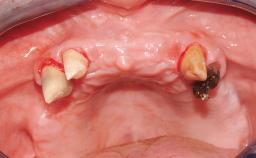

Surgical treatment of a 68-year-old female patient who experienced failure of her conventional bridge in the right maxilla. After removal of the compromised abutment teeth and a healing period of 6 weeks, a sinus floor elevation procedure using the lateral window technique and a composite graft to correct the insufficient bone height is carried out.

Two dental implants are placed in the same surgical session. The case concludes with the presentation of the final fixed dental prosthesis with a distal cantilever unit.